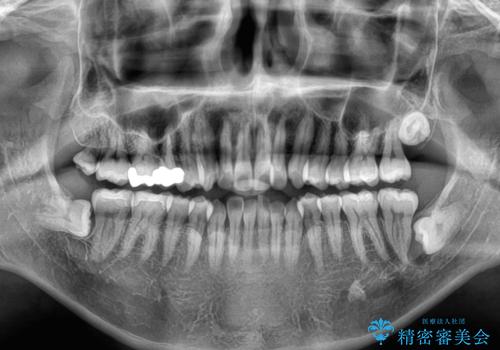

- 前歯の反対咬合などを気にして来院された患者様です。

ワイヤー矯正、マウスピース矯正どちらでも対応可能であったので、ご本人の希望によりインビザラインにて矯正治療を行うこととしました。